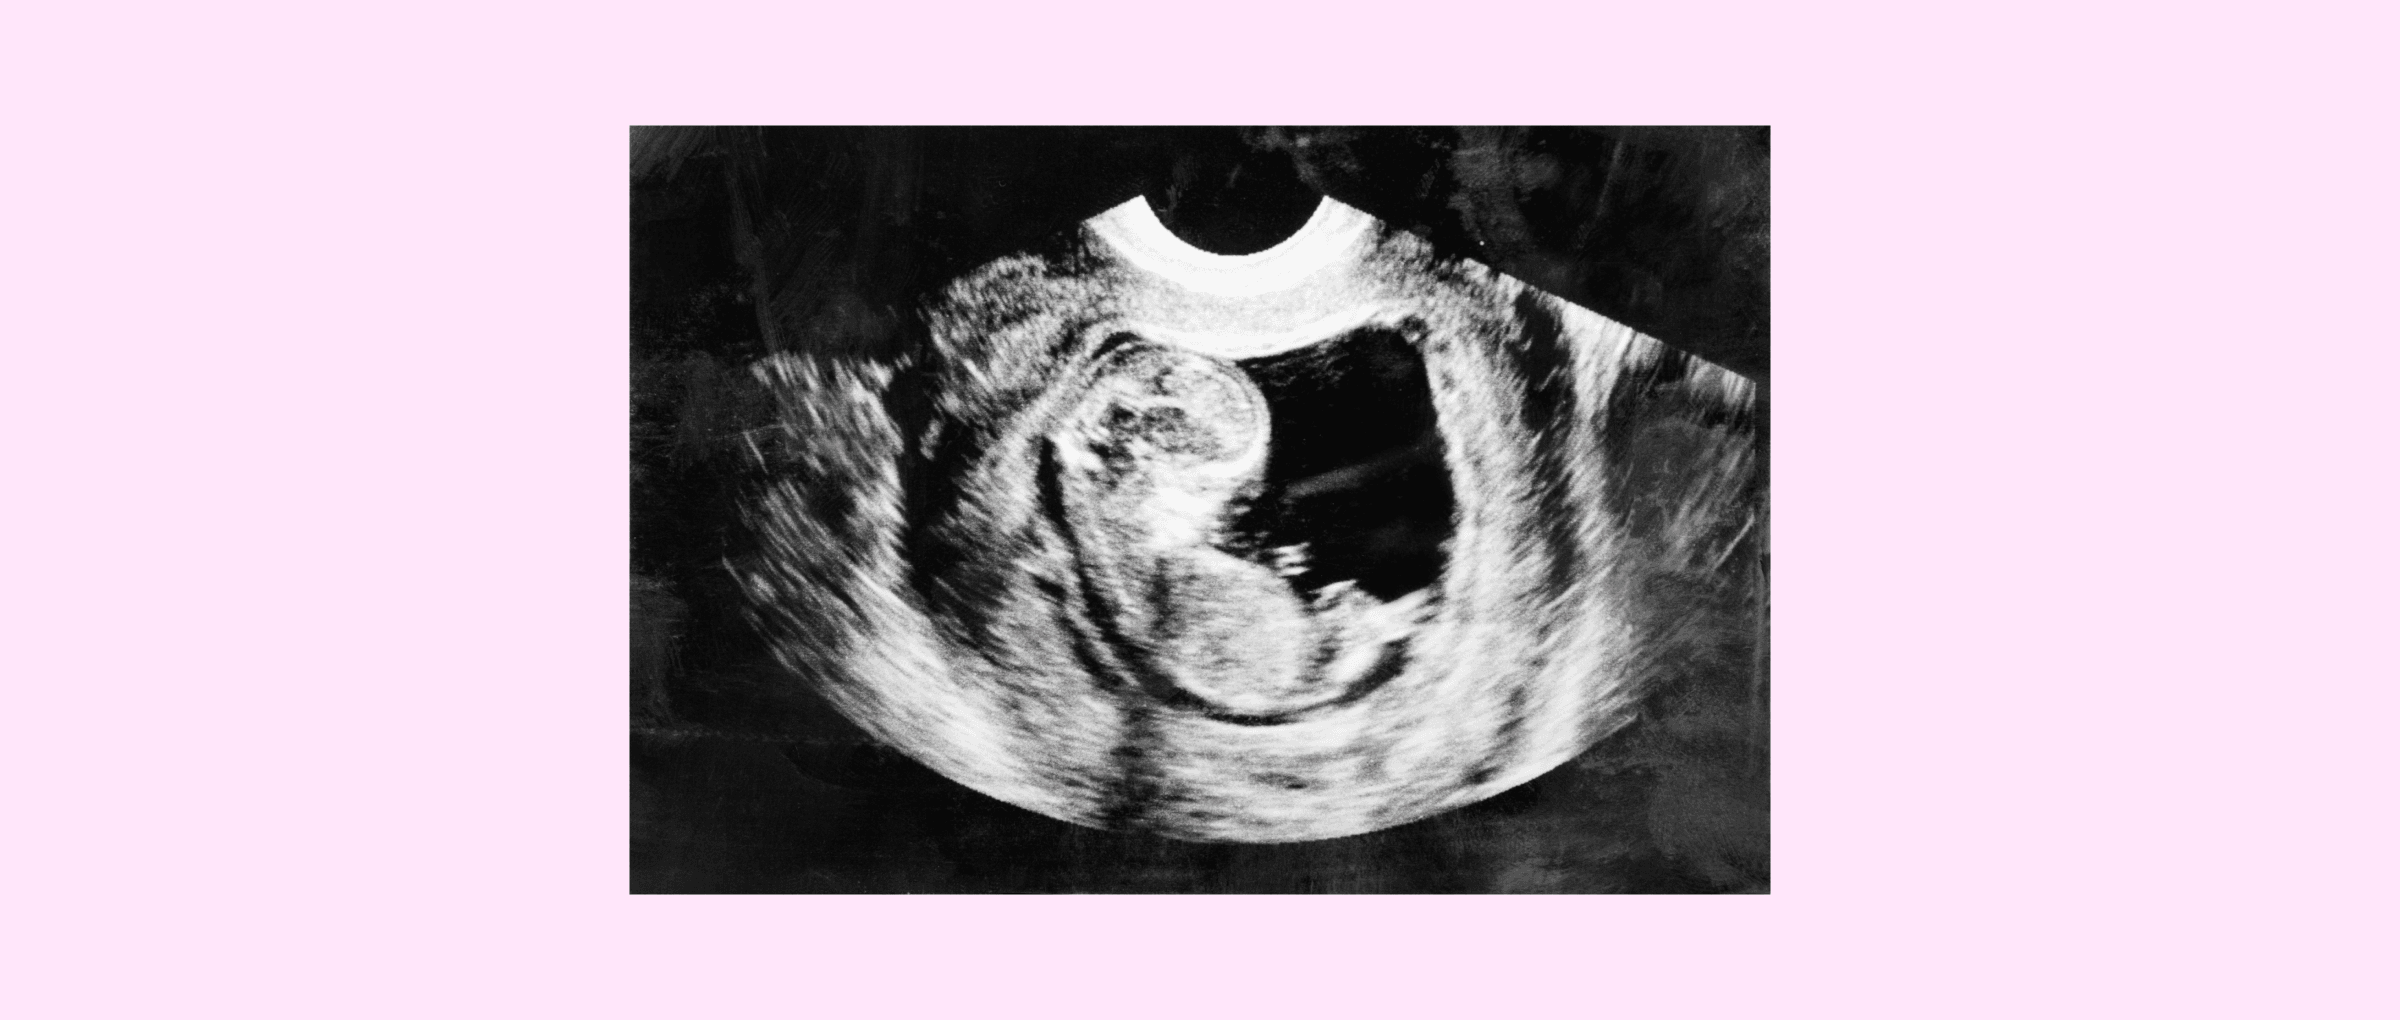

Ecografía

La ecografía de las 12 semanas es una de las más importantes de la gestación, ya que aporta información relevante sobre el estado de salud del bebé y da tranquilidad a los futuros padres.

Entre la multitud de parámetros que permite valorar esta ecografía, destacamos los siguientes:

- Escuchar el latido cardíaco del feto.

- Visualizar el número de fetos y sacos gestacionales, lo que confirma si se trata de un embarazo único o múltiple.

- Tomar las medidas del feto y visualizar las diferentes estructuras de su anatomía.

- Medir la translucencia nucal y el hueso nasal del feto, fundamentales para descartar alteraciones genéticas.

La translucencia nucal o pliegue nucal es la acumulación de líquido debajo de la piel en la parte posterior del cuello del feto, la cual deber ser inferior a los 3 mm.